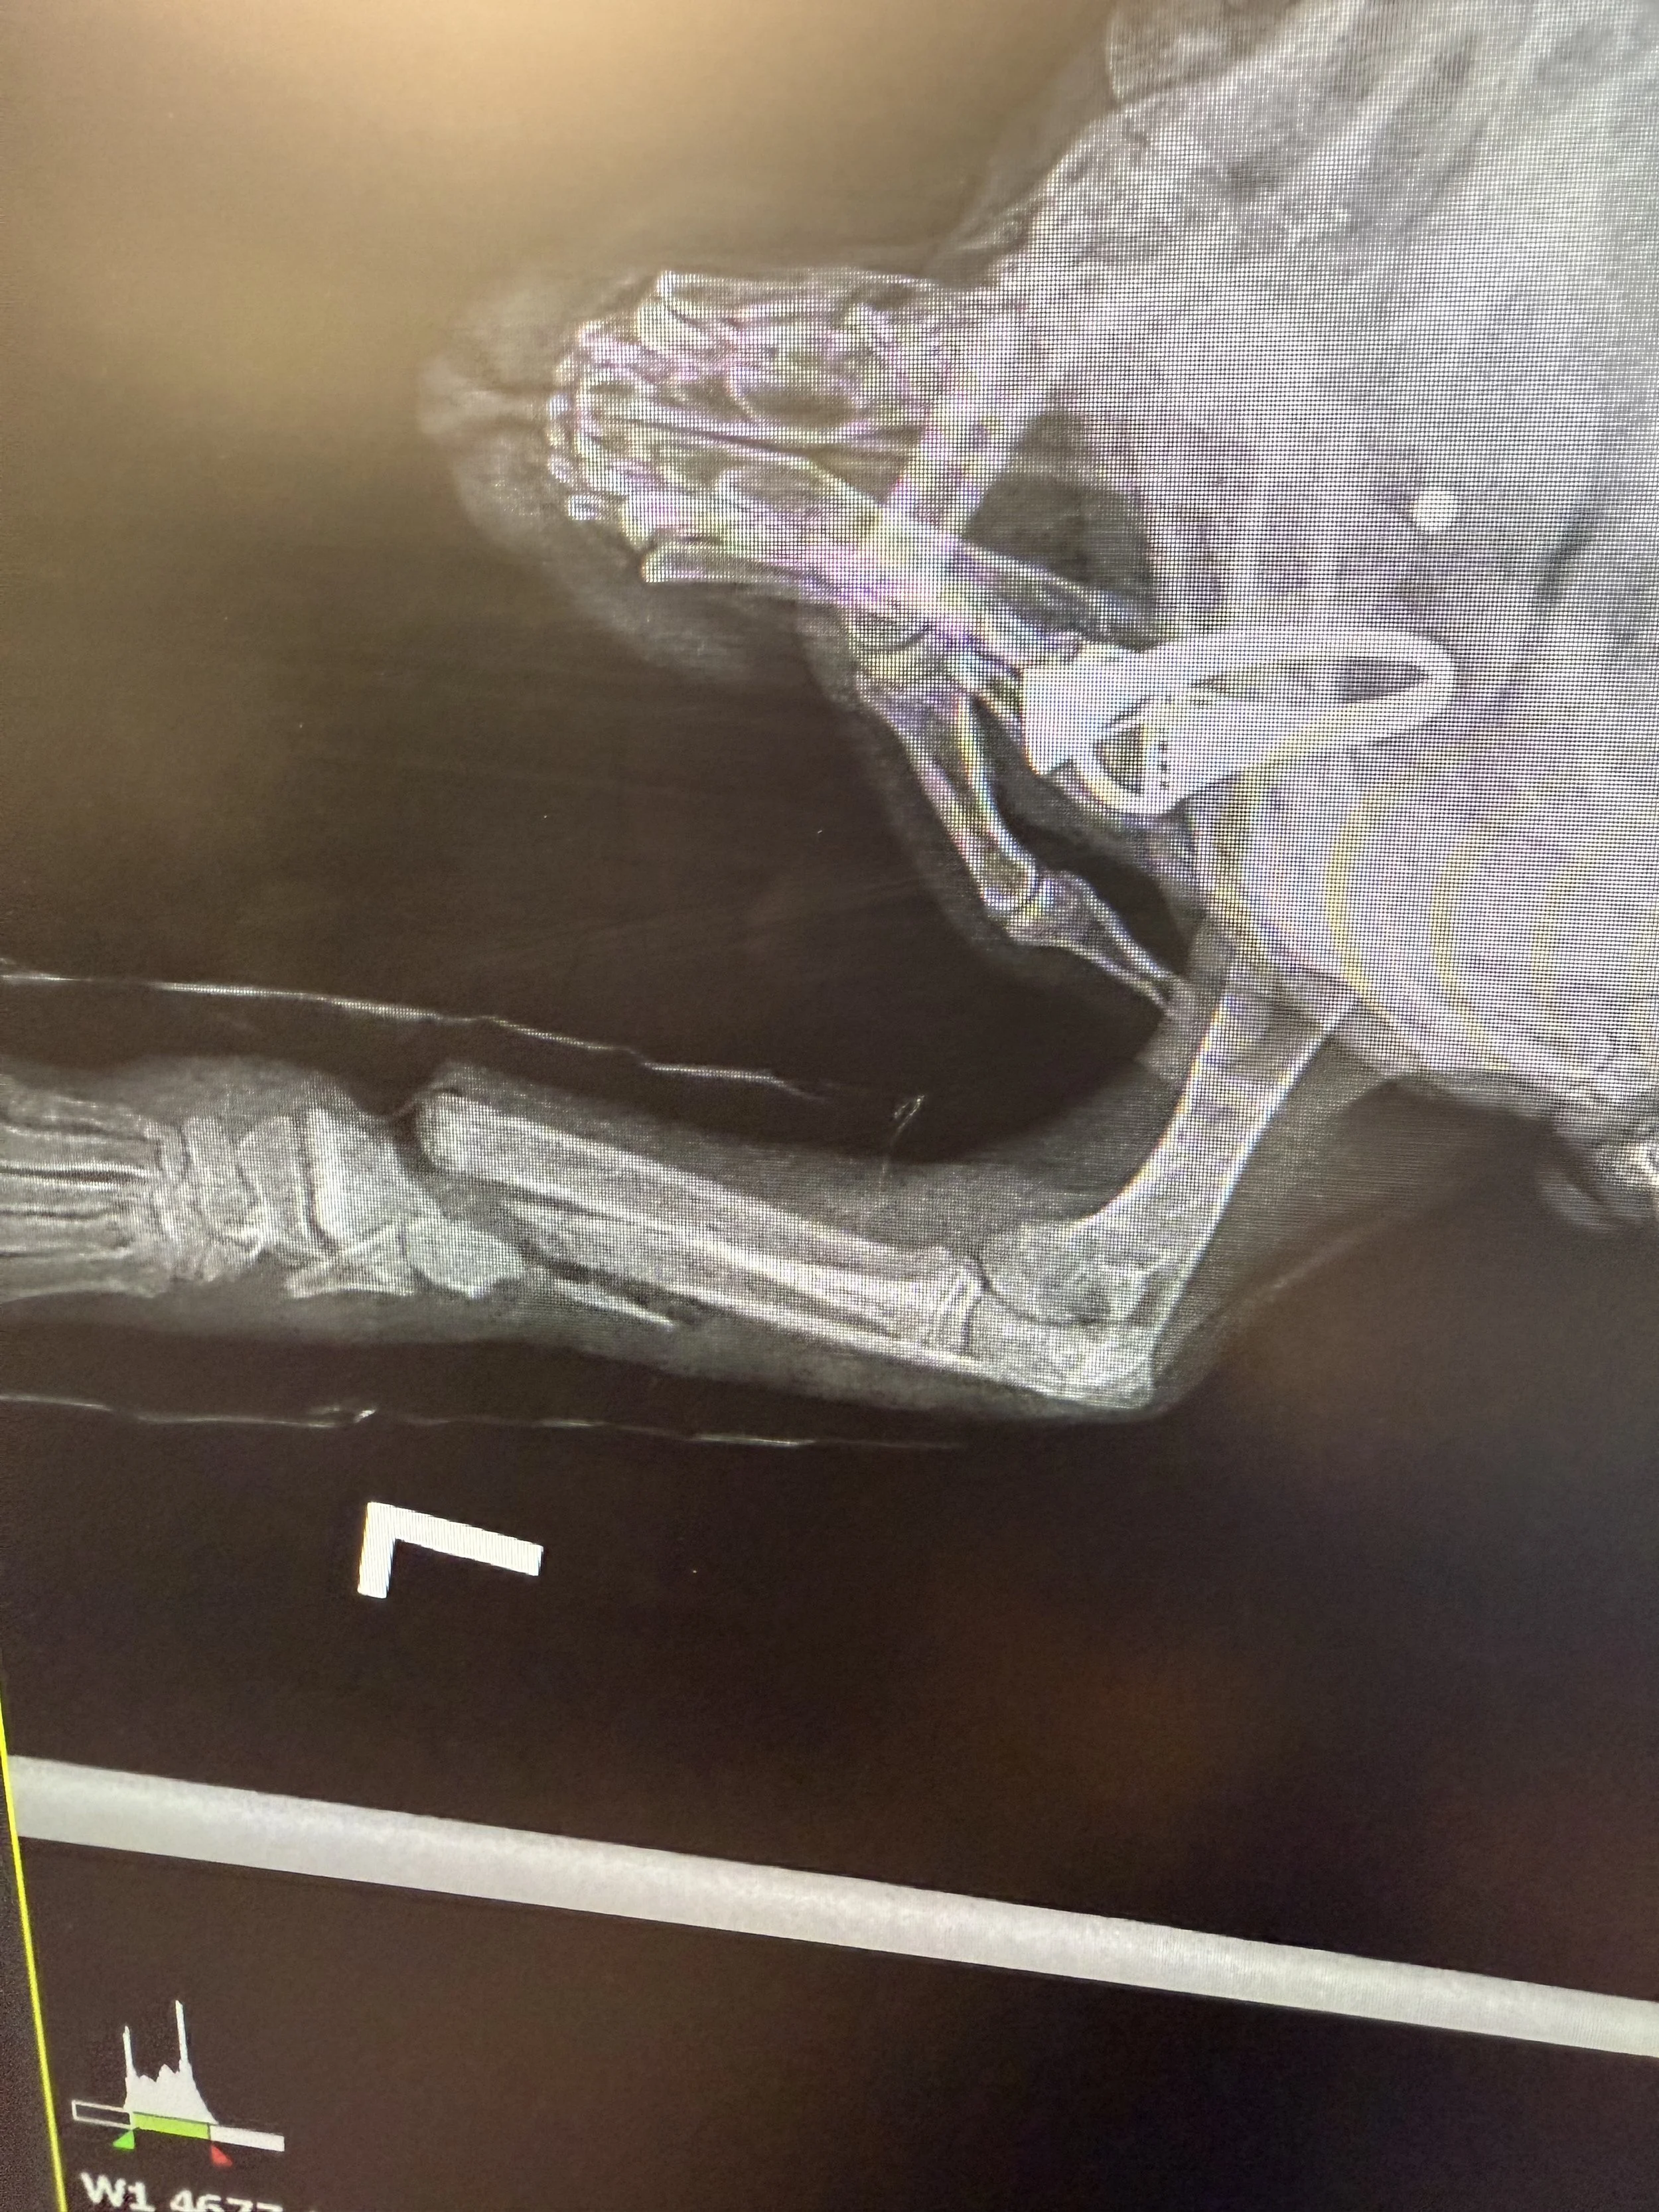

Meet Little Pierre, our newest Ambassador Animal!

This little babe had to have his leg and one of his tiny toes amputated from being caught in a bait trap. We think the hole in his little nose is where mama tried to pull him out of it so we can only imagine how upset she must have been. We're not sure exactly how long he was in the trap (or how long mama tried to pull him free) before a kind person found him and contacted Marybeth here at Mountain Tails Wildlife Rehab.

From the bottom of his little remaining paws, thank you to all for donations and well wishes!